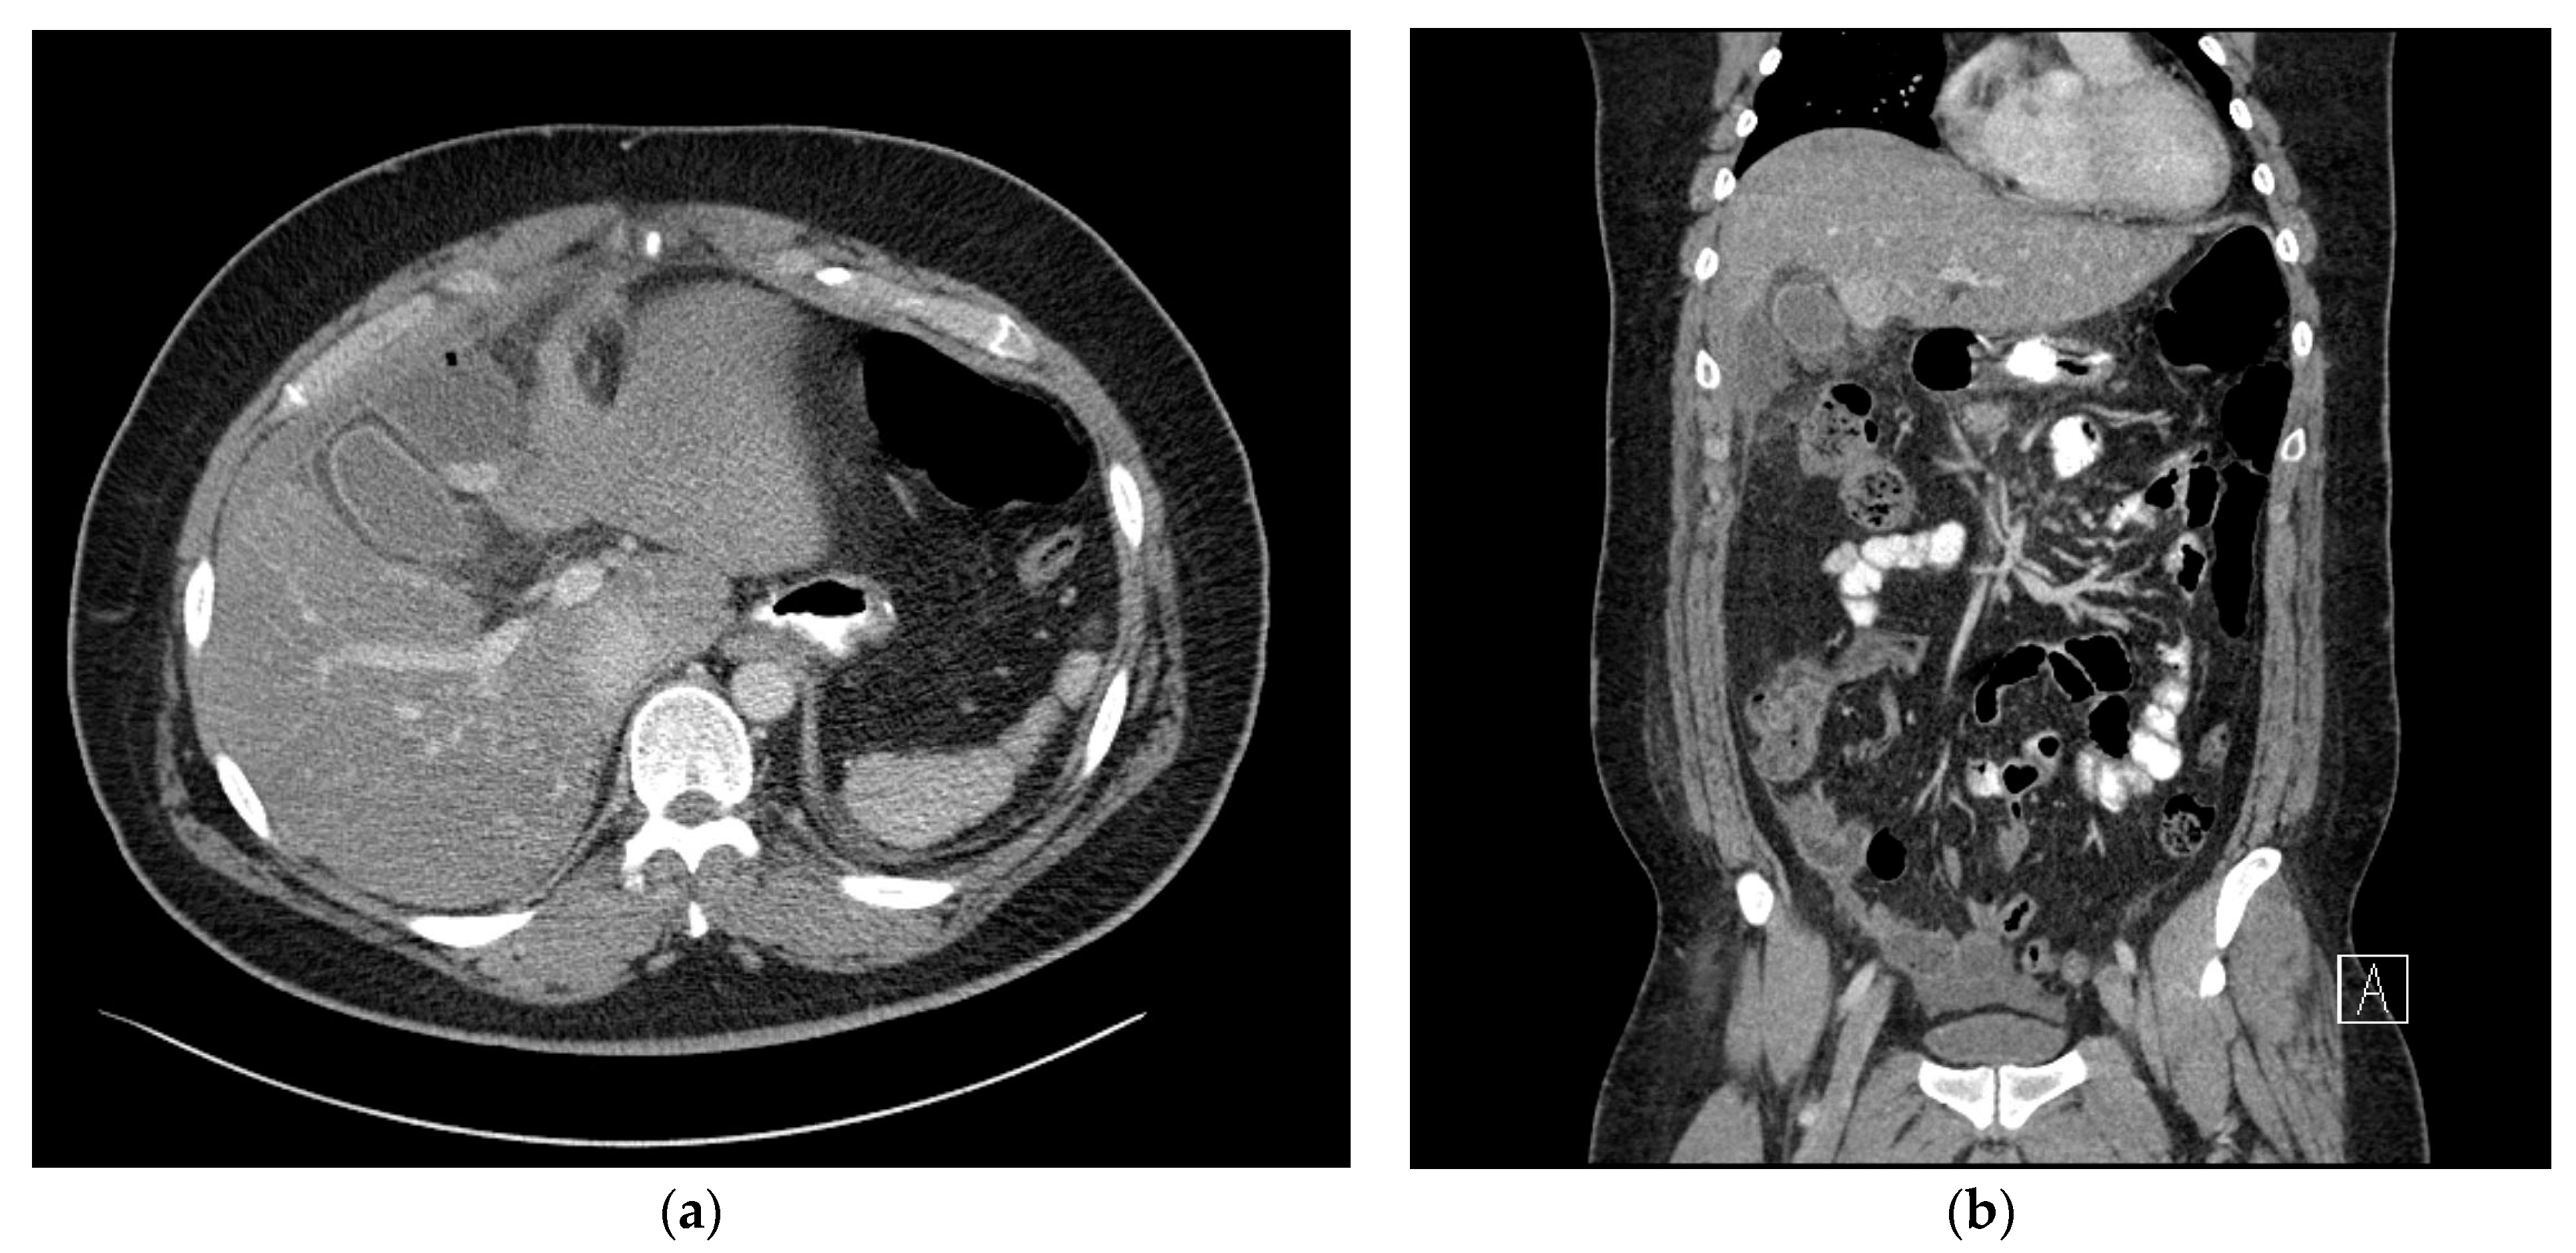

2. Case Presentation